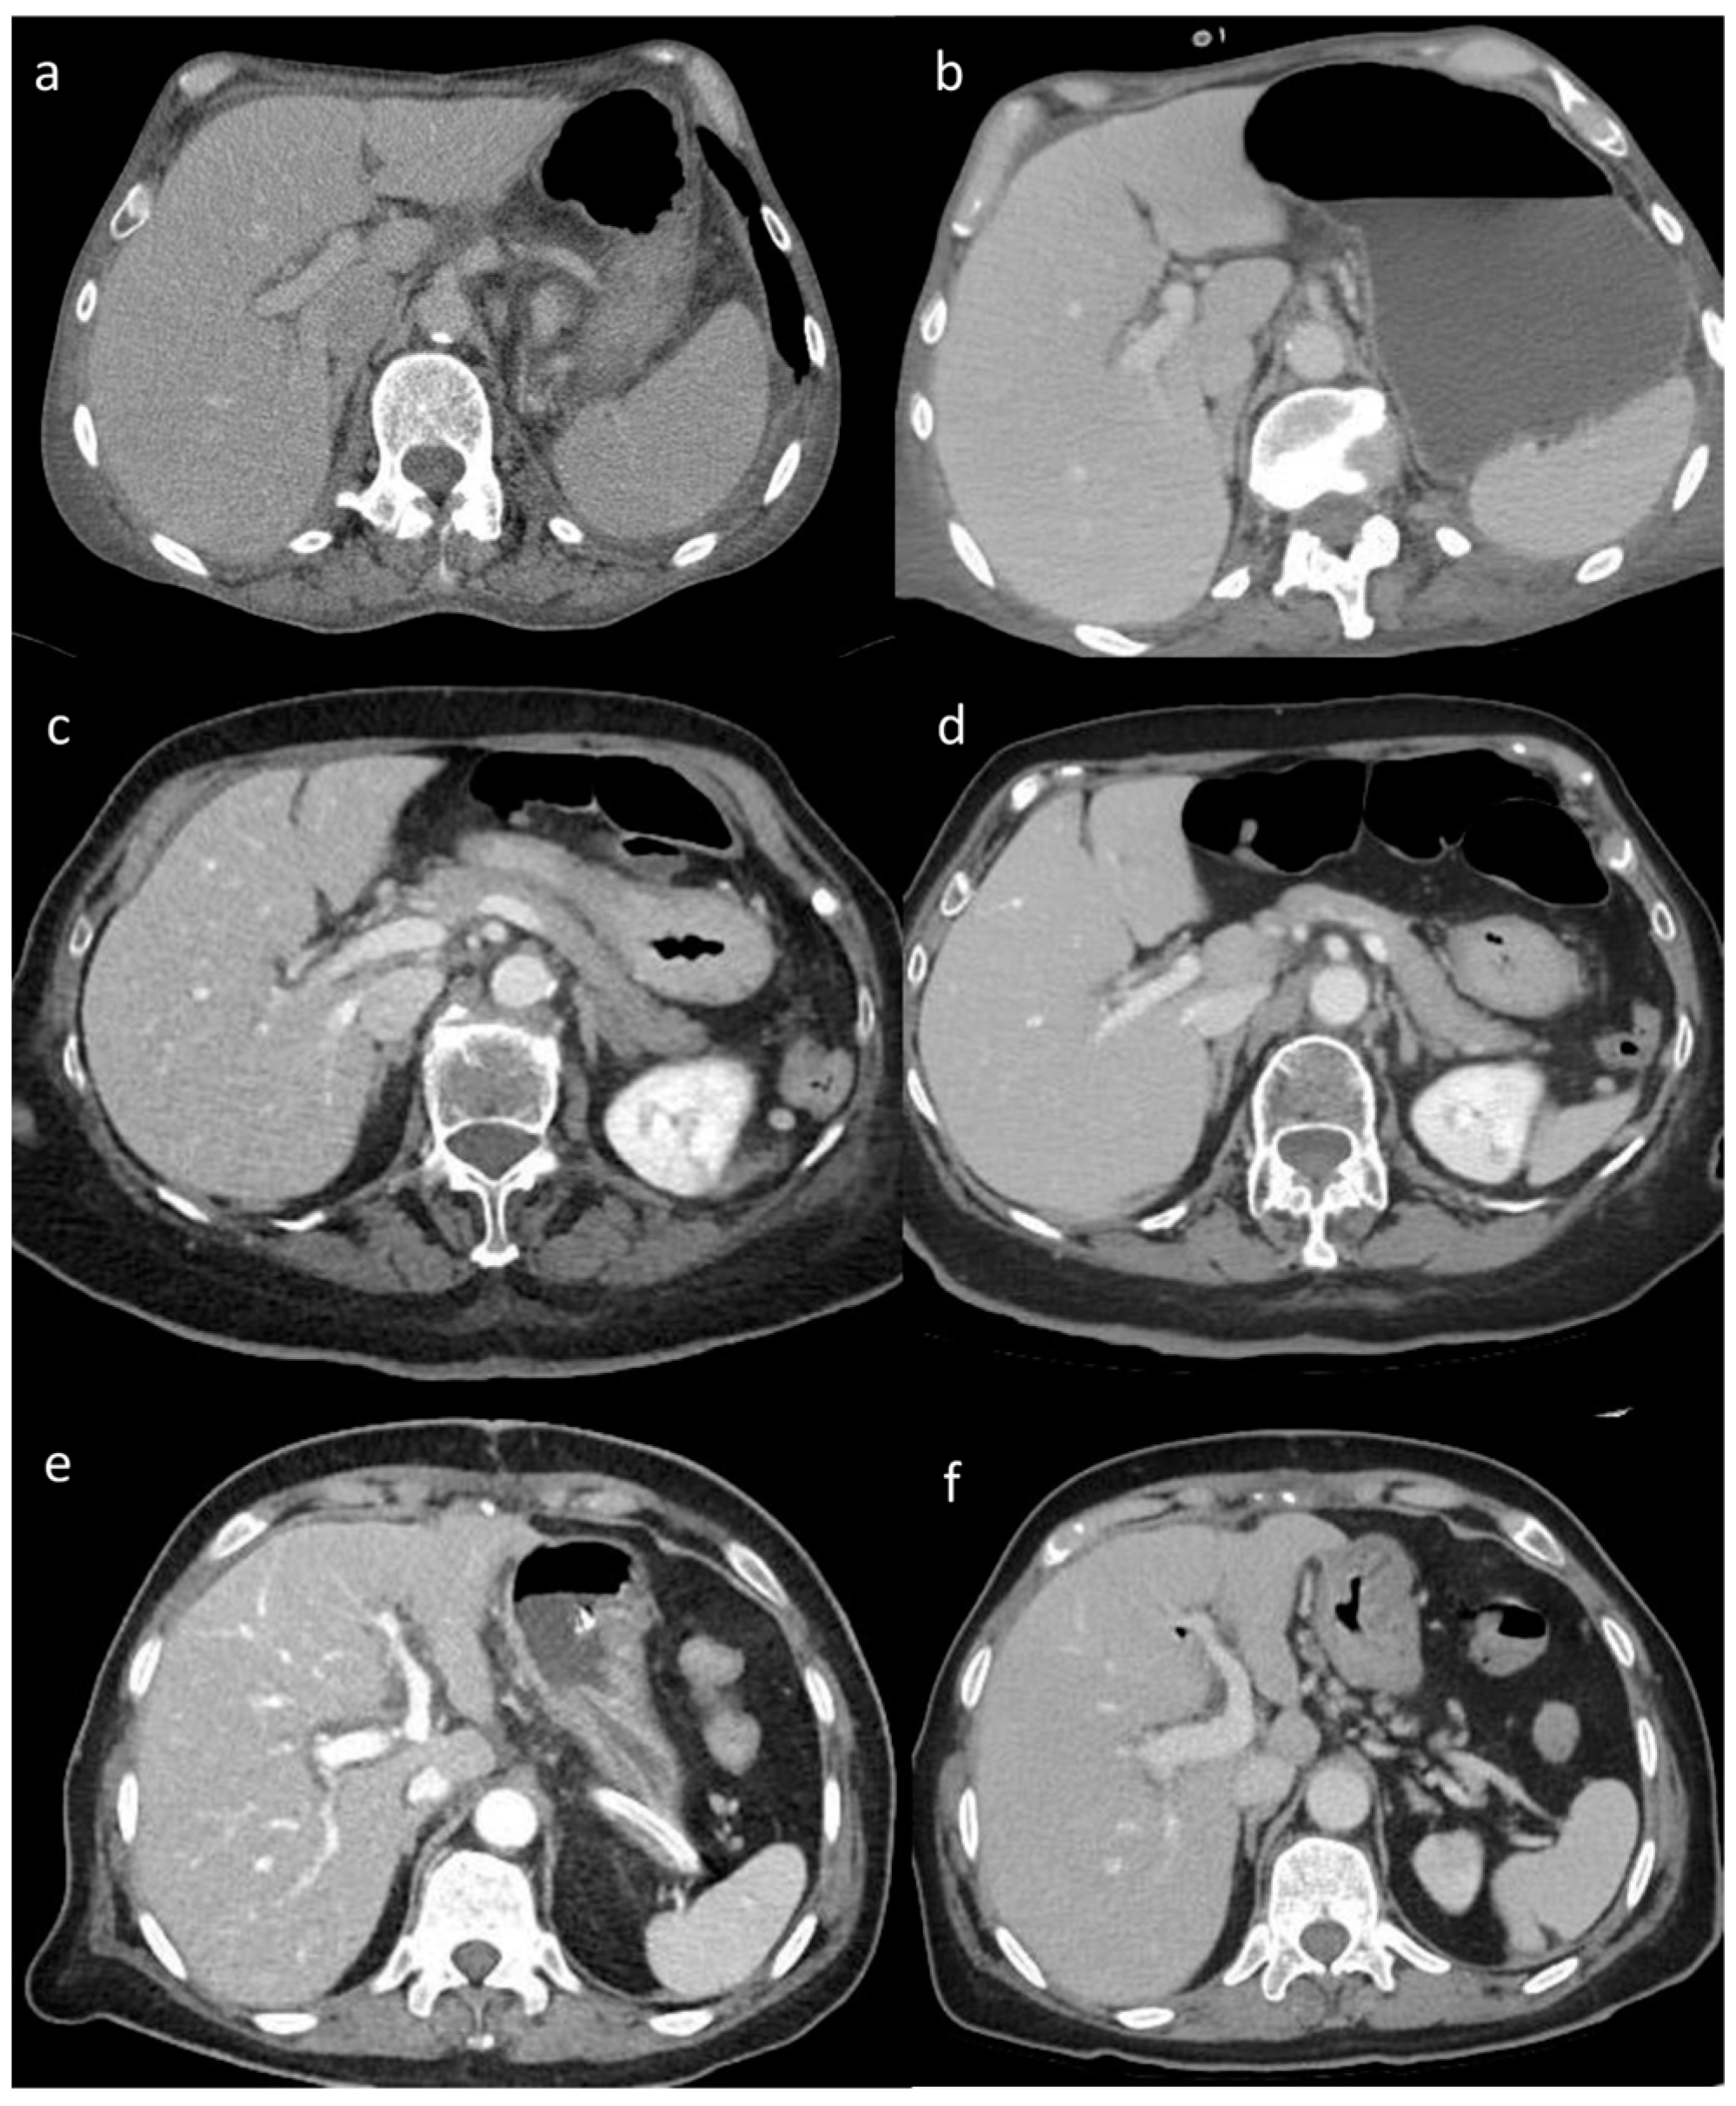

3.2. Visual Analysis

The visual analysis results showed significant differences in the image quality of soft tissue among the three reconstruction methods (all p < 0.05) (Table 4). The image score of DLIR (mean score = 5) was higher than that of ADMIRE (mean score = 4), AIDR 3D (mean score = 3), and FBP (mean score = 3) (Table 4). Both radiologists believed that DLIR had outstanding noise reduction. The subjective scores of the two radiologists were consistent (kappa value range: 0.48–0.91) (Figure 2).

Figure 2. (af) Visual analysis. Visual differences in abdominal parenchyma border definition and noise among different reconstruction algorithms: (a,b) 45-year-old male patient after major surgery; (c,d) 47-year-old male patient after lung transplant; and (e,f) 55-year-old male patient after cardiac transplant. Filtered back projection (FBP) (a), Advanced Modeled Iterative Reconstruction (ADMIRE) model-based iterative reconstruction (c), and Adaptive Iterative Dose Reduction 3D (AIDR 3D) hybrid iterative reconstruction (e) vs. deep learning image reconstruction (DLIR) (b,d,f). FBP, ADMIRE, and AIDR 3D were scored as 2, 4, and 3, respectively, whereas DLIR images were scored as 5 by all reviewers.